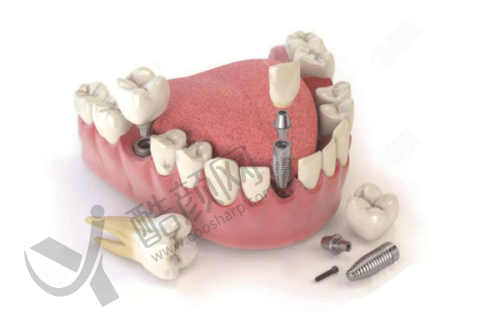

史衡涛医生在种植牙领域有着深厚的造诣,其技术水平非常可靠。他擅长全口种植牙、半口种植牙、单颗种植、多颗种植以及即刻种植牙等多种种植技术。在临床实践中,面对不同患者复杂的口腔状况,他都能精细分析并制定出更适合的种植方案。